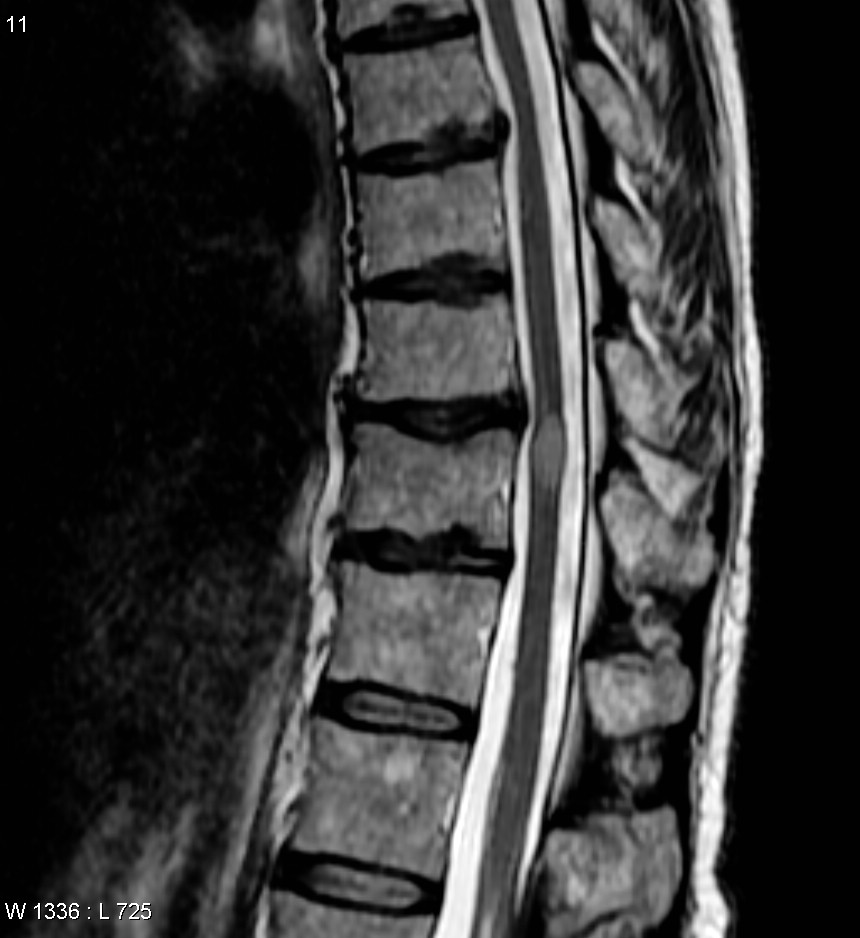

Transverse_myelitis_MRI Published at 860 × 938 in Fifty Shades of Grey [matter] ~ interpreting MRIs « Previous T-2 – CSF (cerebral spinal FLUID) INTENSE, great for visualizing bulging discs and degeneration.